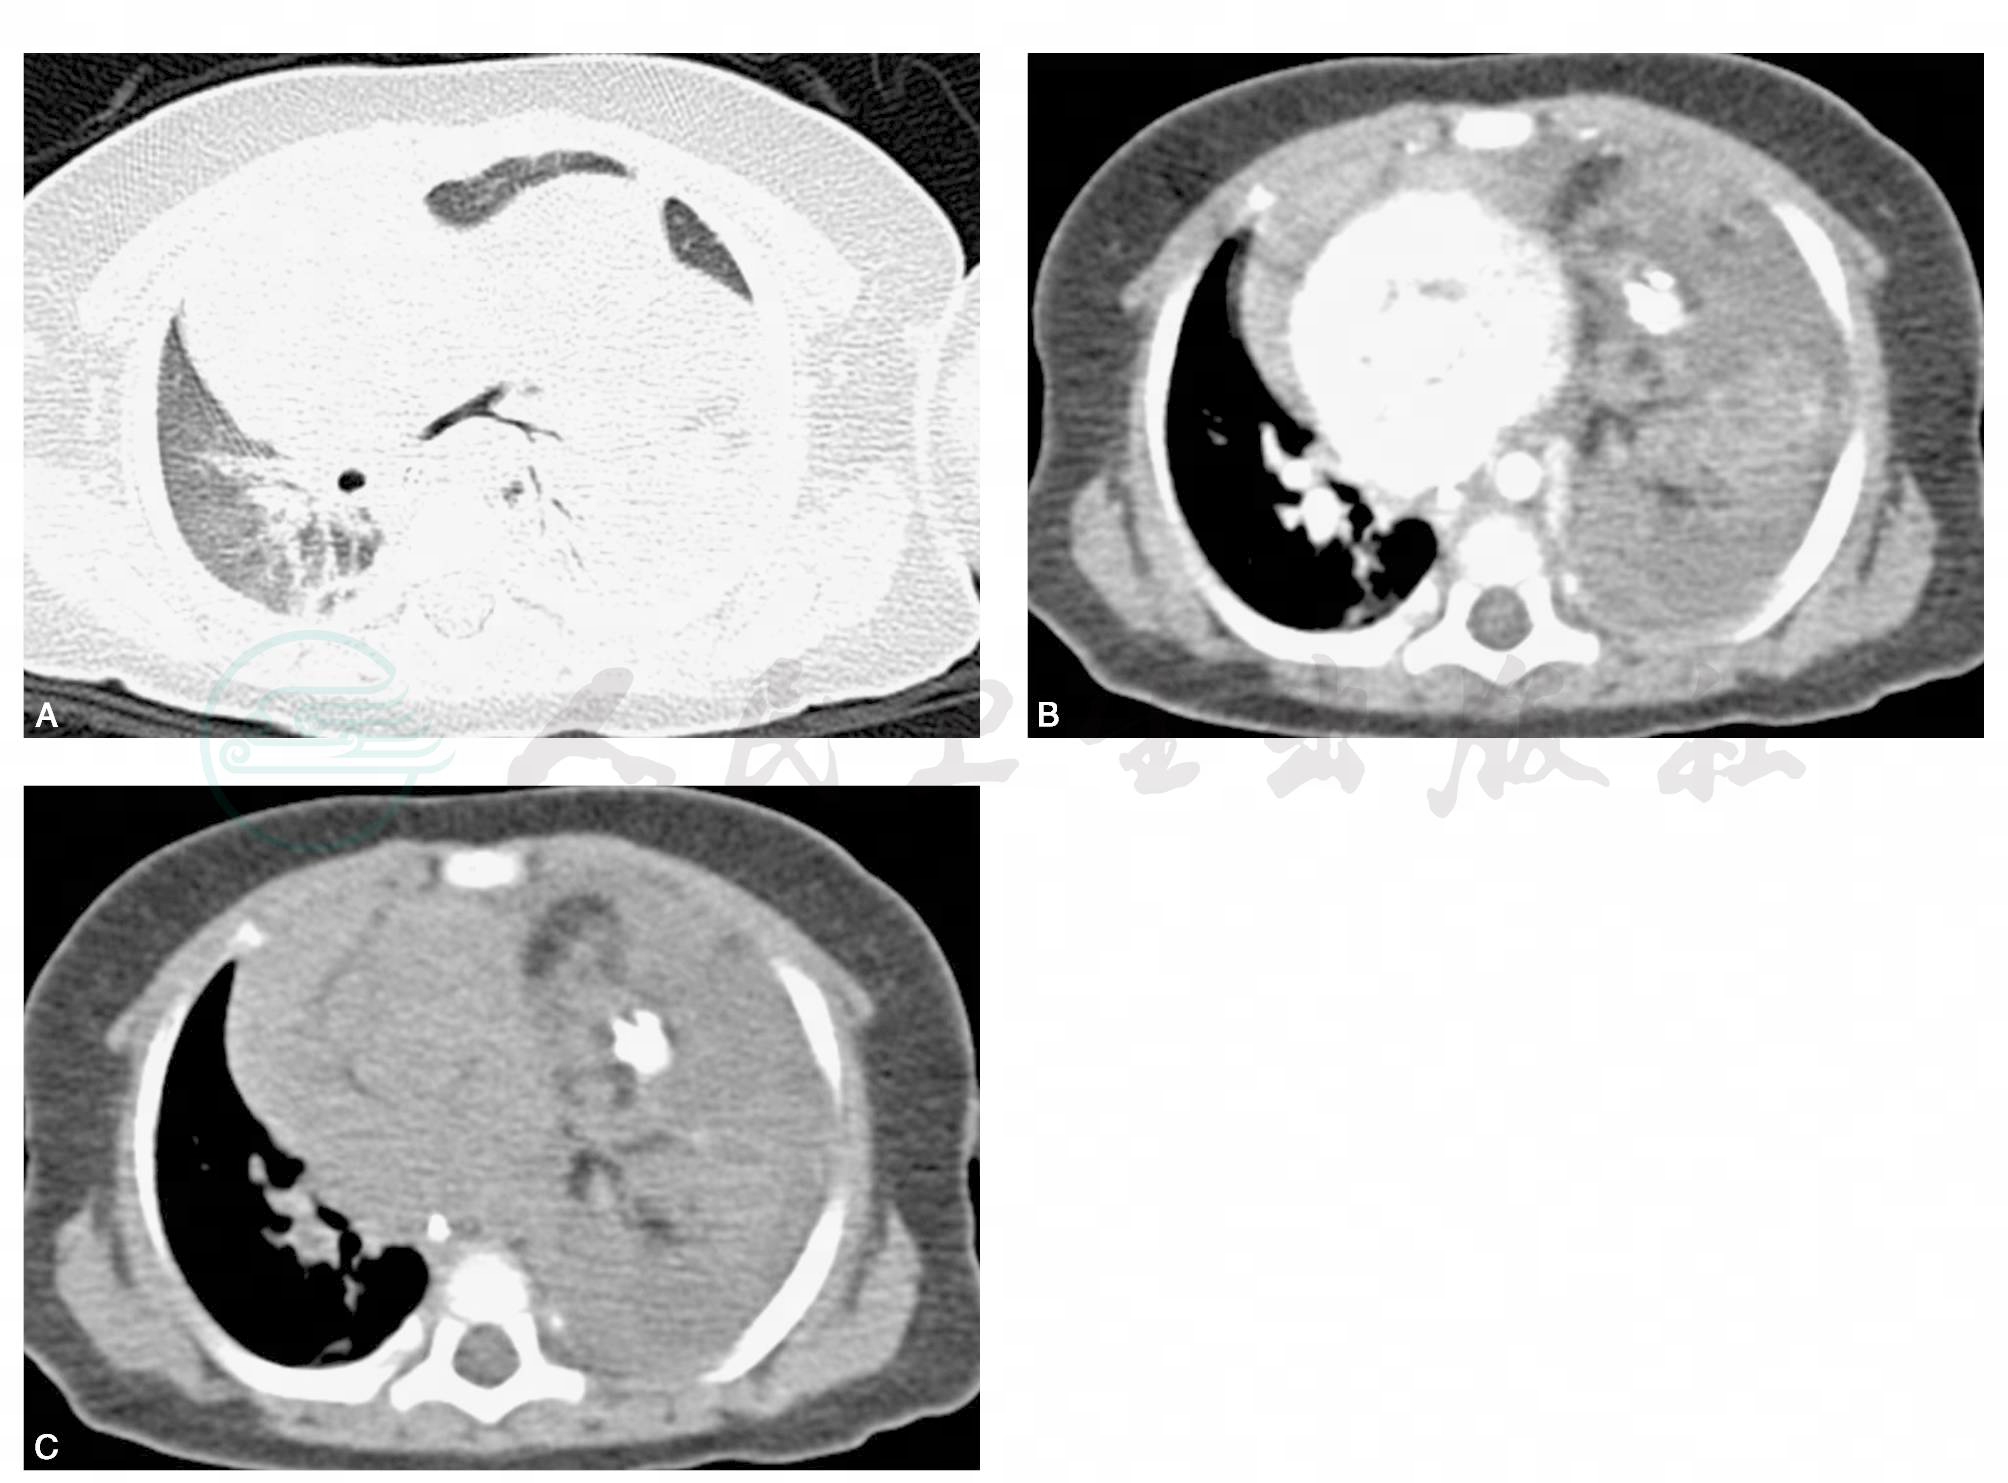

【病例2介绍】

女,30岁,患者以“体检发现左上纵隔占位一周”为主诉入院。患者体检发现左上纵隔占位,时有咳嗽咳痰,黄痰量多,无明显胸闷气短,无乏力,无胸背痛,胸CT提示左上纵隔占位。后行胸部增强CT扫描提示左前纵隔占位病变,畸胎瘤可能性大。于2010年6月13日行纵隔肿物切除术,患者术后恢复良好(图2)。

图2 平扫纵隔窗示囊性占位内部密度不均,内见多个小钙化密度影。增强扫描示囊壁轻度强化,其内低密度区未见强化